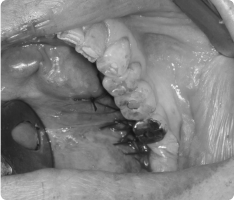

- 국소마취 후 잇몸을 열어 낭종과 함께 원인 치아를 제거합니다.

- 낭종 벽을 깨끗이 적출하여 재발을 막습니다.

- 병리검사를 통해 정확한 진단을 확인합니다.

- 작은 경우는 간단히 제거가 가능하고, 큰 경우는 단계적으로 치료하기도 합니다.